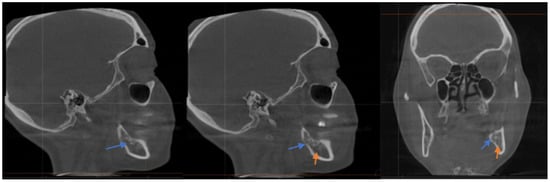

She sought a second opinion 4 months post-surgery, and she was found to have anesthesia on the left distribution of IAN with intense shock-like pain, consistent with anesthesia dolorosa because of probable IAN damage. The CBCT showed that the xenograft was packed into the base of the socket, which was in direct contact with the IAN, and thus mineralized bovine bone was found to be completely compressing the nerve in the wisdom tooth area (see Figure 2). We discussed the distinct options for management ranging from pharmacological management to surgical intervention; however, she was already on medication for her MS, and the surgical option would involve a sagittal split osteotomy on the left side to try to free the nerve with the possibility of permanent numbness without any guarantee of success, so she was not in favor of the surgery. The patient described her pain stemming from the center of her numb lower left lip and chin region as intense and episodic, though the sensation to her tongue had returned. The patient also reported that the shock-like pain had recently spread over the left maxillary area as well.

Figure 2. Sagittal CT scan: Note the proximity of the mineralized xenograft in tooth #17 (Blue Arrow) following surgical removal and bone graft procedure to inferior alveolar nerve canal (Orange Arrow).